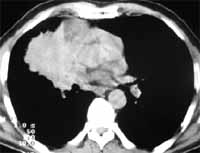

Figura 3. Carcinoma de célula pequeña parahiliar derecho.

Dentro de las características clínicas de este tipo de tumor se encuentran la gran proporción de síndromes paraneoplásicos asociados a éstos, como son el de Eaton-Lambert (17), secreción inadecuada de hormona antidiurética, síndrome de Cushing y otros (23). Dentro de la sintomatología general se pueden presentar síntomas constitucionales (23).